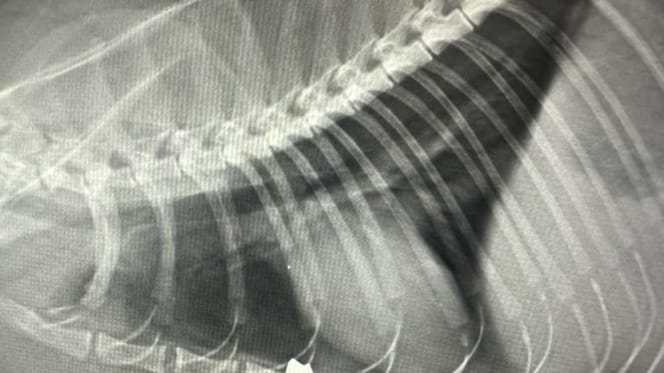

Dopiero zdjęcie rentgenowskie ujawnia okrutną prawdę: w klatce piersiowej Mausi tkwi śrut diabolo – pocisk z wiatrówki!

„Z zewnątrz nic nie było widać” – potwierdza lekarka weterynarii, podkreślając podstępny charakter rany. Prawdopodobnie zwierzę zostało postrzelone od tyłu, a pocisk obrócił się w ciele, powodując rozległe obrażenia tkanek.

Zdjęcie rentgenowskie pokazuje, jak niewiarygodnie dużo szczęścia w nieszczęściu miała kotka. Pocisk zatrzymał się dosłownie milimetry od serca. Serce i płuca cudem nie zostały uszkodzone. Gdyby śrut przemieścił się choć odrobinę dalej, Mausi już by nie żyła!